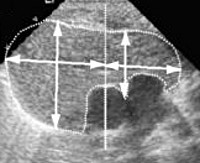

Тимомегалия: что это такое и как проявляется